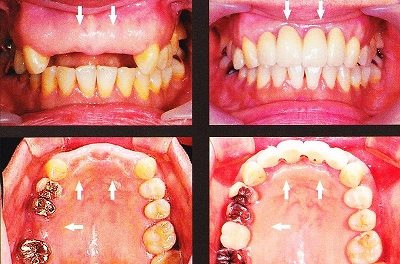

前歯の無い症例

1本欠損症例

![]()